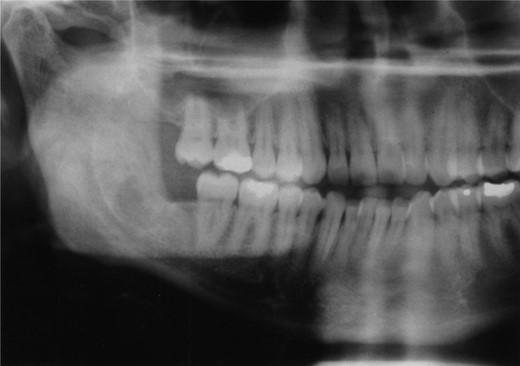

Plain films along with CT scan, with 3 mm slices, were performed a further year later and showed good bone regeneration in the right ramus and condylar neck (Figs 4 and 5). No evidence of cystic recurrence was seen and no abnormalities within the adjacent soft tissues. High-resolution magnetic resonance imaging also confirmed the absence of cystic remnants. The patient has now been reviewed for 5 years and there is no evidence of recurrence.